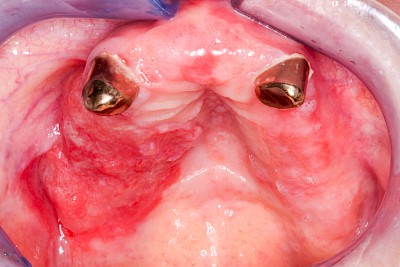

Prothesenstomatitis

Rötung im Bereich der Prothesen-Auflageflächen

Großfläche Rötungen sind häufig auf chronische Entzündungsprozesse bedingt durch die ständige Auflage der Prothese auf der Schleimhaut mitunter 24 Stunden am Tag zurückzuführen (feuchte Kammer). Ganz selten sind spezifische Unverträglichkeistreaktionen wie z. B. Allergien gegen Inhaltsstoffe der Prothesenmaterialien die Ursache. Alle diese Prozesse können unter dem Oberbegriff Prothesenstomatitis zusammengefasst werden.

Druckstelle / Lappenfibrom

Eine besondere Form der Verletzung entsteht, wenn eine Zahnprothese ungleichmäßig und punktuell auf Kieferbereiche drückt. Die sogenannten Druckstellen erscheinen wie kleine Druckgeschwüre (vergleichbar dem Dekubitus z. B. an Fersen oder im Bereich der Hüftknochen) auf.